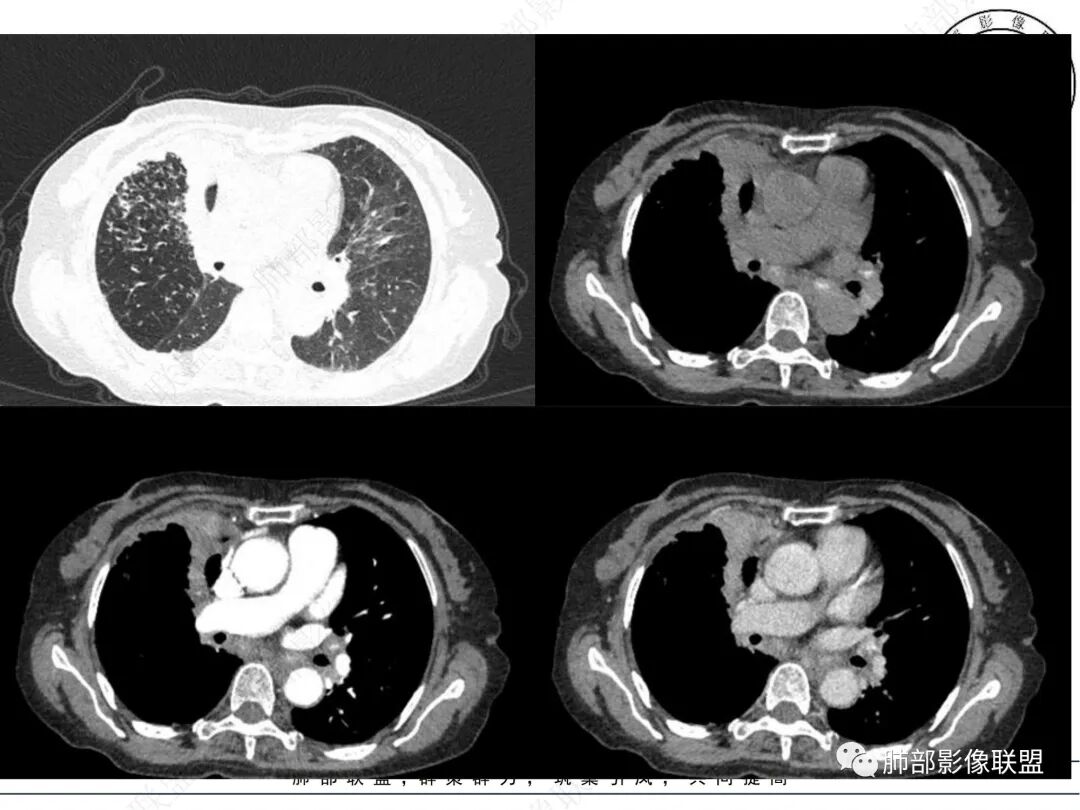

2. CT示右肺上叶多发斑片状实变影,结节影,集群散落,夹杂条索影,边界可分辨,有沿支气管血管束分布趋势,可见树芽征。病灶新旧不等、密度不均。右上叶支气管壁不均匀节段性增厚狹窄,斑点状钙化。纵隔旁部分肺组织含气不良,并显示轻度扩张支气管。病灶邻近胸膜增厚,轻度强化。

3.余双肺显示马赛克灌注、轻度气肿。双肺散在微小实行密度结节影,边界清楚。

4.纵隔多发增大淋巴结,部分融合、钙化。

成簇分布斑片影、结节影、树芽征,边界较清楚,新旧不等,节段性支气管壁增厚伴钙化,管腔狭窄,纵隔及肺门淋巴结增大钙化等都较符合“继发性肺结核、支气管内膜结核”诊断。